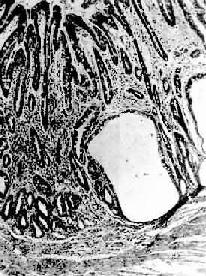

镜下,病变区腺上皮萎缩,腺体变小并可有囊性扩张,常出现上皮化生(假幽门腺化生及肠上皮化生)。在粘膜固有层有不同程度的淋巴细胞和浆细胞浸润。在胃体和胃底部病变区,主要呈现壁细胞消失,其次是主细胞消失和粘液分泌细胞化生。后者称为幽门腺或假幽门腺化生。电镜观察,壁细胞除数量减少外,可见细胞内自噬泡增多,内质网扩张,高尔基器减少,线粒体肿胀,表面微绒毛消失。内质网、高尔基器和微绒毛是壁细胞的功能部分,其减少或消失反映了细胞泌酸功能的低下或消失。在幽门窦病变区,主要改变为幽门腺呈不同程度的萎缩、消失(图10-3)并常有肠上皮化生。胃粘膜表层上皮细胞生长,可形成绒毛样突起,增生的上皮中出现分泌粘液的杯状细胞(图10-4)、具有刷状缘的吸收上皮细胞和Paneth细胞时其形态结构与小肠粘膜相似,故称为肠上皮化生。现知肠上皮化生的胃粘膜易诱发胃,多为息肉样腺

图10-3 慢性萎缩性胃炎

幽门腺大部分萎缩消失,胃小凹延长,有潴留性小囊形成,腺上皮中杂有不少杯状细胞(肠上皮化生),固有膜内有不少慢性炎性细胞浸润(Ⅱ74-4950)